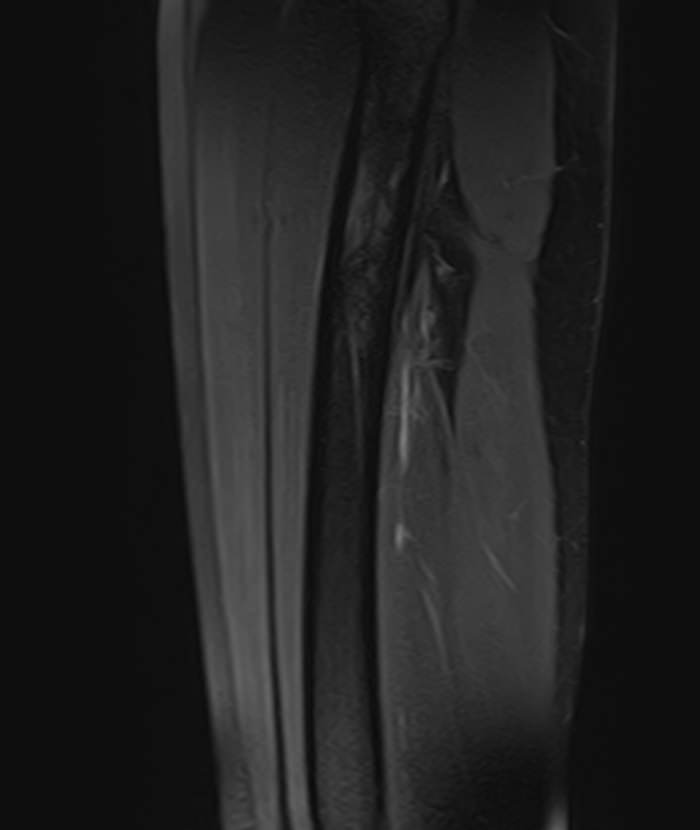

- Закрытые и открытые травматические повреждения (ушибы, гематомы, растяжения связок, разрывы мышц, повреждения сосудов и нервов).

Чаще всего ягодичная область подвержена развитию воспалительных заболеваний, травматических повреждений и опухолевых процессов. Наиболее эффективным способом диагностики патологии мягких тканей ягодичной области является магнитно-резонансная томография. При применении данного метода не используется вредное ионизирующее излучение, как при обычном рентгене или КТ, при этом МРТ дает наибольшую информацию о состоянии мягкотканных структур, выявляя патологические очаги размером от 1 мм.